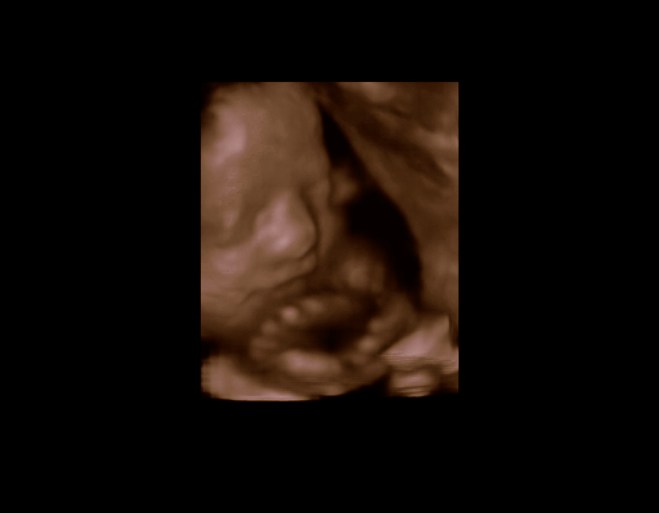

Prøv lige at se hvordan min lækre pige smiler til fotografen. Er det ikke bare fantastisk sjovt? Jeg vidste slet ikke at fostre kunne smile på den måde...

Netop. Hun vejede også en del over gennemsnittet fortalte skanningsdamen, så hun har intet at være ked af over